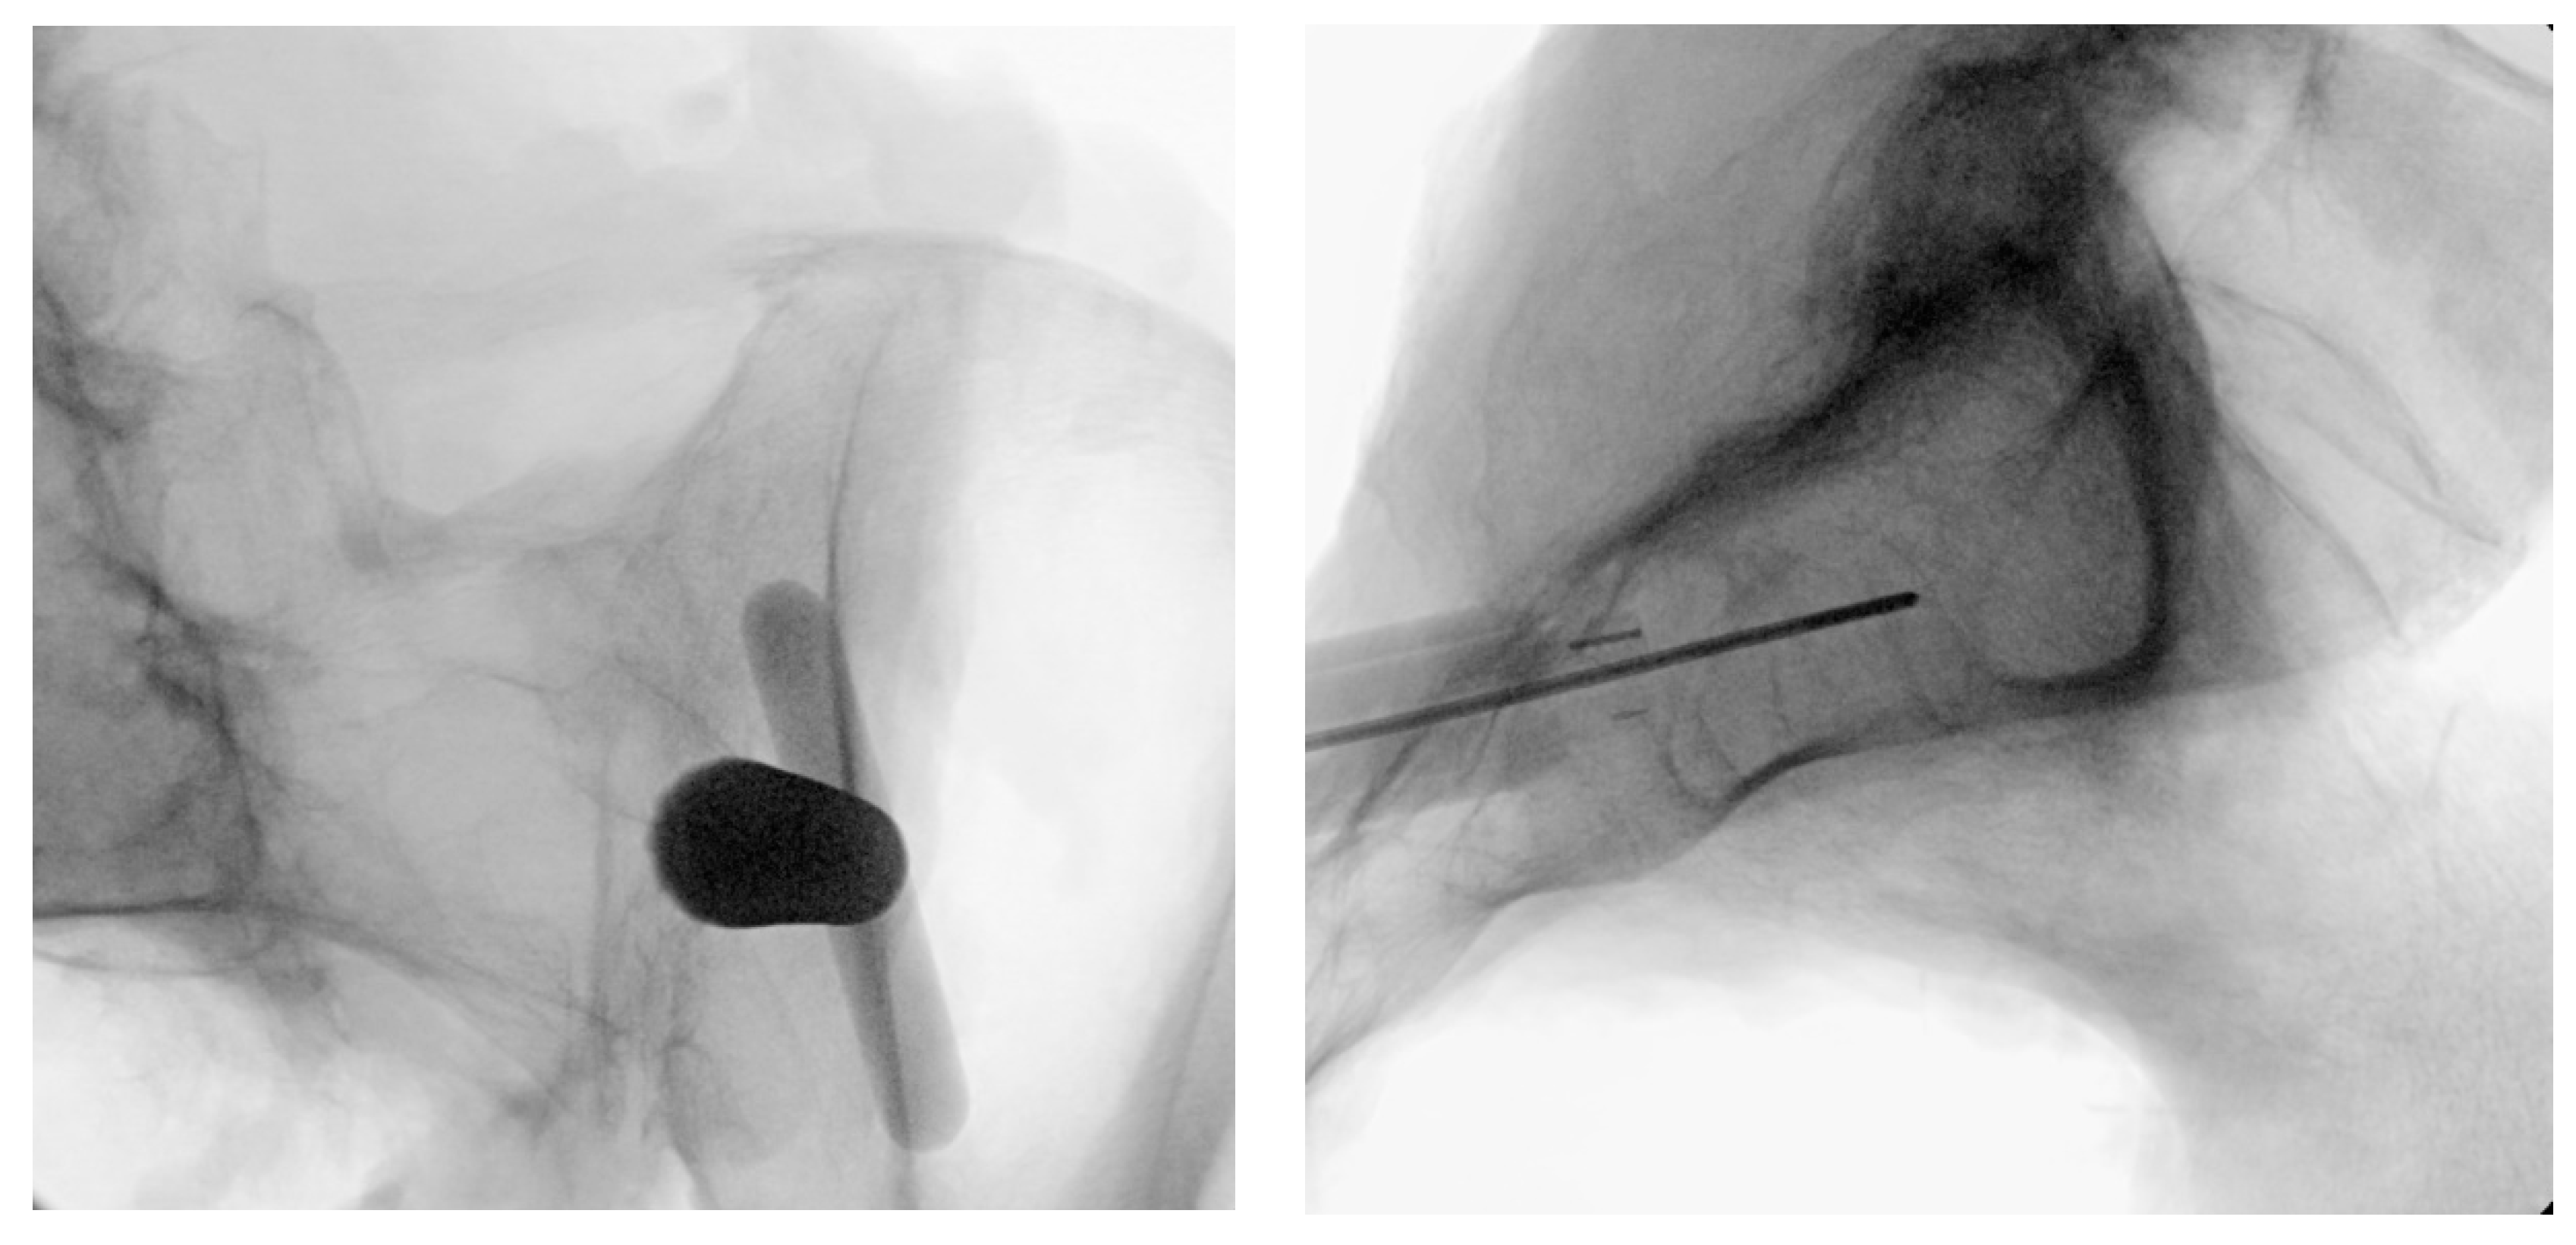

Figure 3. Oblique (left), and lateral (right) fluoroscopic views indicating the initial proper introduction and placement of the Steinmann pin into the SIJ.

Under fluoroscopic guidance using the inlet view, advance a Steinmann pin starting inferior, ventral, and lateral to the PSIS, and advancing superiorly, through the ilium across the SI joint into the sacrum. Finally, use a lateral fluoroscopic view to verify that the tip of the Steinmann pin has passed the posterior cortical outline of the sacrum, and is docked in the sacrum at or near center of the first sacral body (Figure 3).